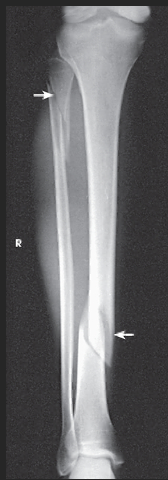

AP leg (tib fib)

What SID is used?

48 inches

What anatomy is placed parallel to the IR?

Patella and femoral condyles

What position is the patient in?

Supine w/ foot dorsiflexed

What anatomy must be included on the radiograph?

Entire tibia and fibula plus adjacent joints

What should be done if the entire tib/fib cannot fit on the IR?

Either rotate the IR to be diagonal to the leg OR take two separate images (a bigger image of whichever joint is more in pain and a smaller image of the other joint)

How far beyond the adjacent joints should you see light?

1.5"

What part of the tib/fib should be free of superimposition?

Fibula midshaft

Lateral leg (tib-fib)

What type of projection is it?

Mediolateral

48"

Describe the position of the patient.

recumbent onto the affected side; keep the knee slightly flexed to obtain a true lateral

What anatomy must be ⟂ to the IR?

Femoral condyles and patella

Where does the CR enter?

Perpendicular to the midpoint of the leg

What must be seen on the radiograph?

Entire tibia and fibula with adjacent joints

Describe how to evaluate for a true lateral.

Distal fibula superimposed by posterior half of tibia; slight overlap between tibia and fibular head; separation of tibial and fibular bodies (not at ends)